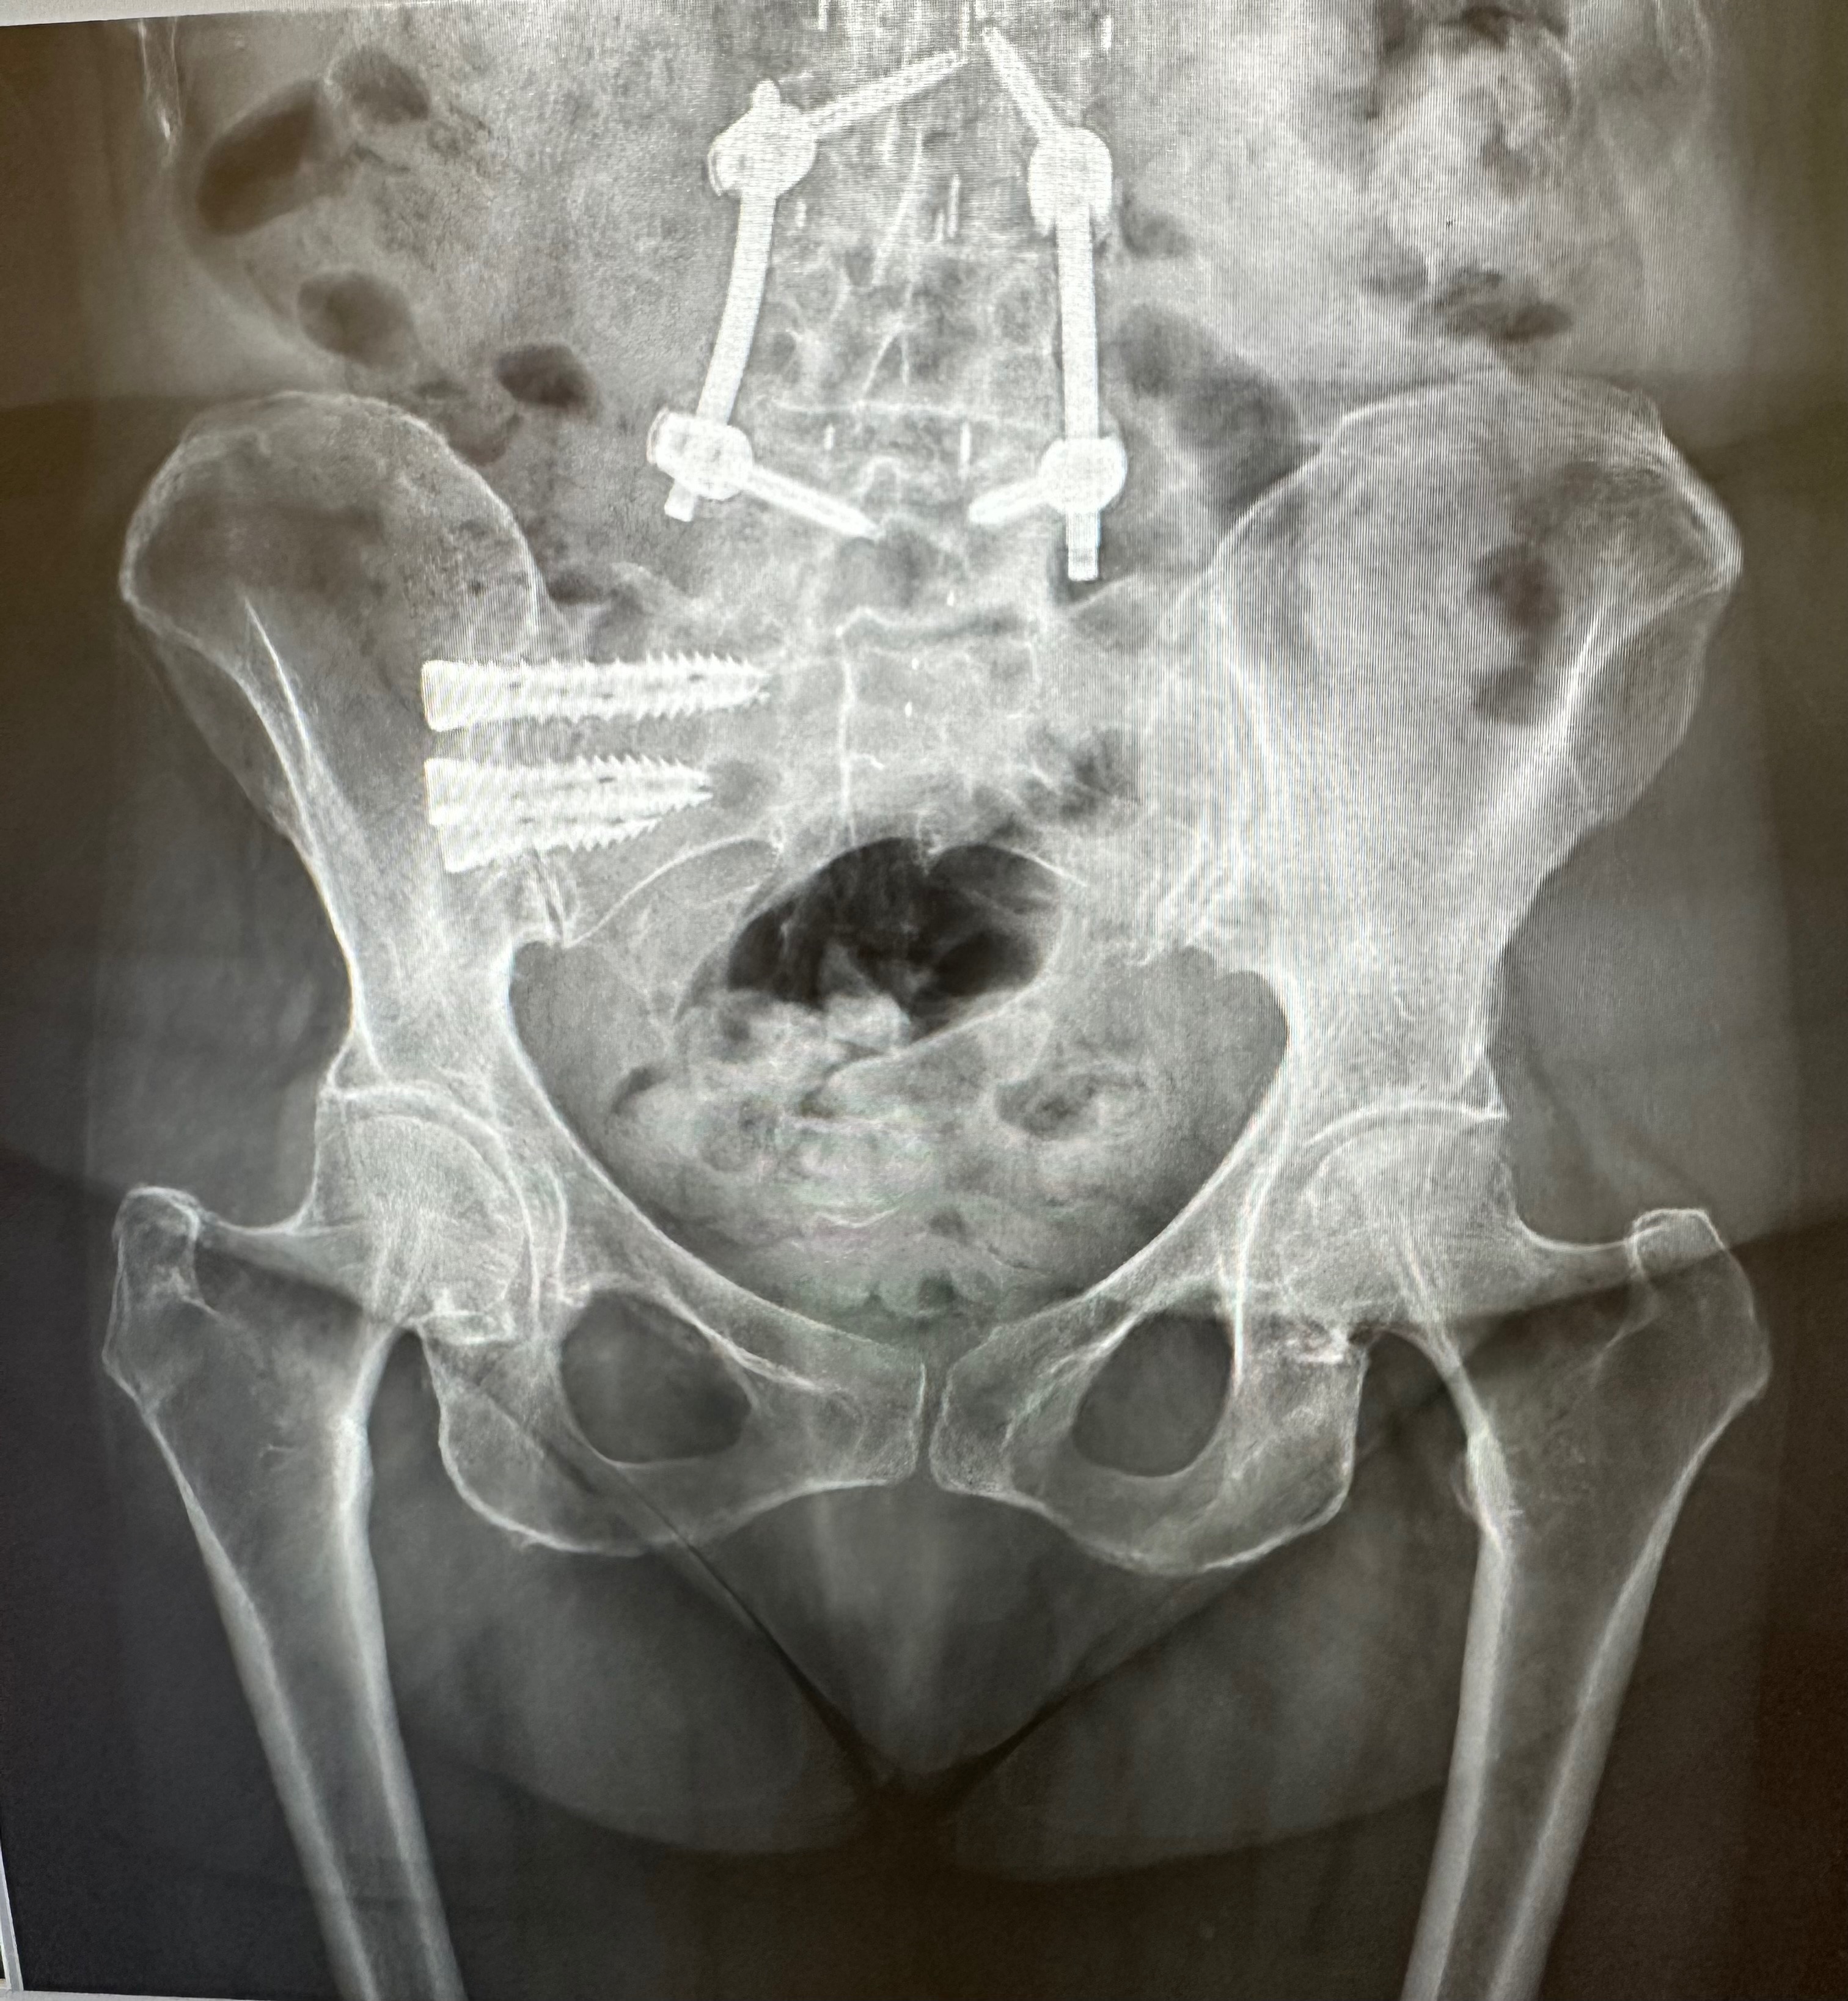

Lori has survived more surgeries than she can count but her hope remains strong. We are asking for your help to try one last treatment. Recent failed surgeries and setbacks have caused chronic pain leading to trouble walking with a cane. She has severe tears to her gluteus medius and minimus on her right hip, along with other bone and joint issues throughout her body. We found a top surgeon with a 90% success rate, but Medicare will not cover this treatment. Lori dreams of the day she can move without constant pain—not just for herself but for the animals who depend on her. Her greatest joy has always been caring for cats and dogs who need a second chance.

Lori’s double tendon reconstruction, is scheduled for January 22, 2026, where she will be in a hip and leg brace for 24/7 (except showers) for six weeks (she has been to this rodeo before with her surgery in January 2024 and this is the worst part of the recovery process), with thrice weekly physical therapy treatments. What makes Dr. Sanjum Samagh success rate 90% is his use of these three added procedures during surgery that we are asking for help with today. (Medicare will pay 100% of balance of surgery).